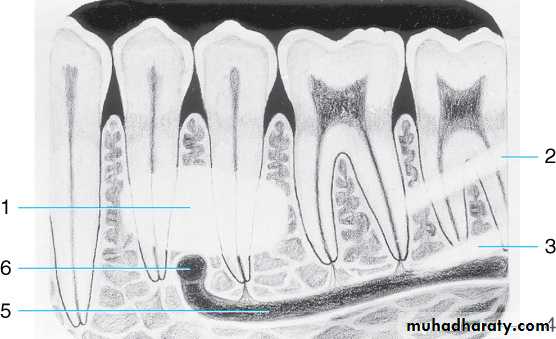

Teeth are composed of pulp (arrow on the secondmolar), enamel (arrow on the first molar), dentin (arrow onthe second premolar), and cementum (usually not visibleradiographically).

Alveolar crestLamina dura

Periodontal ligament space

Cancellous bone